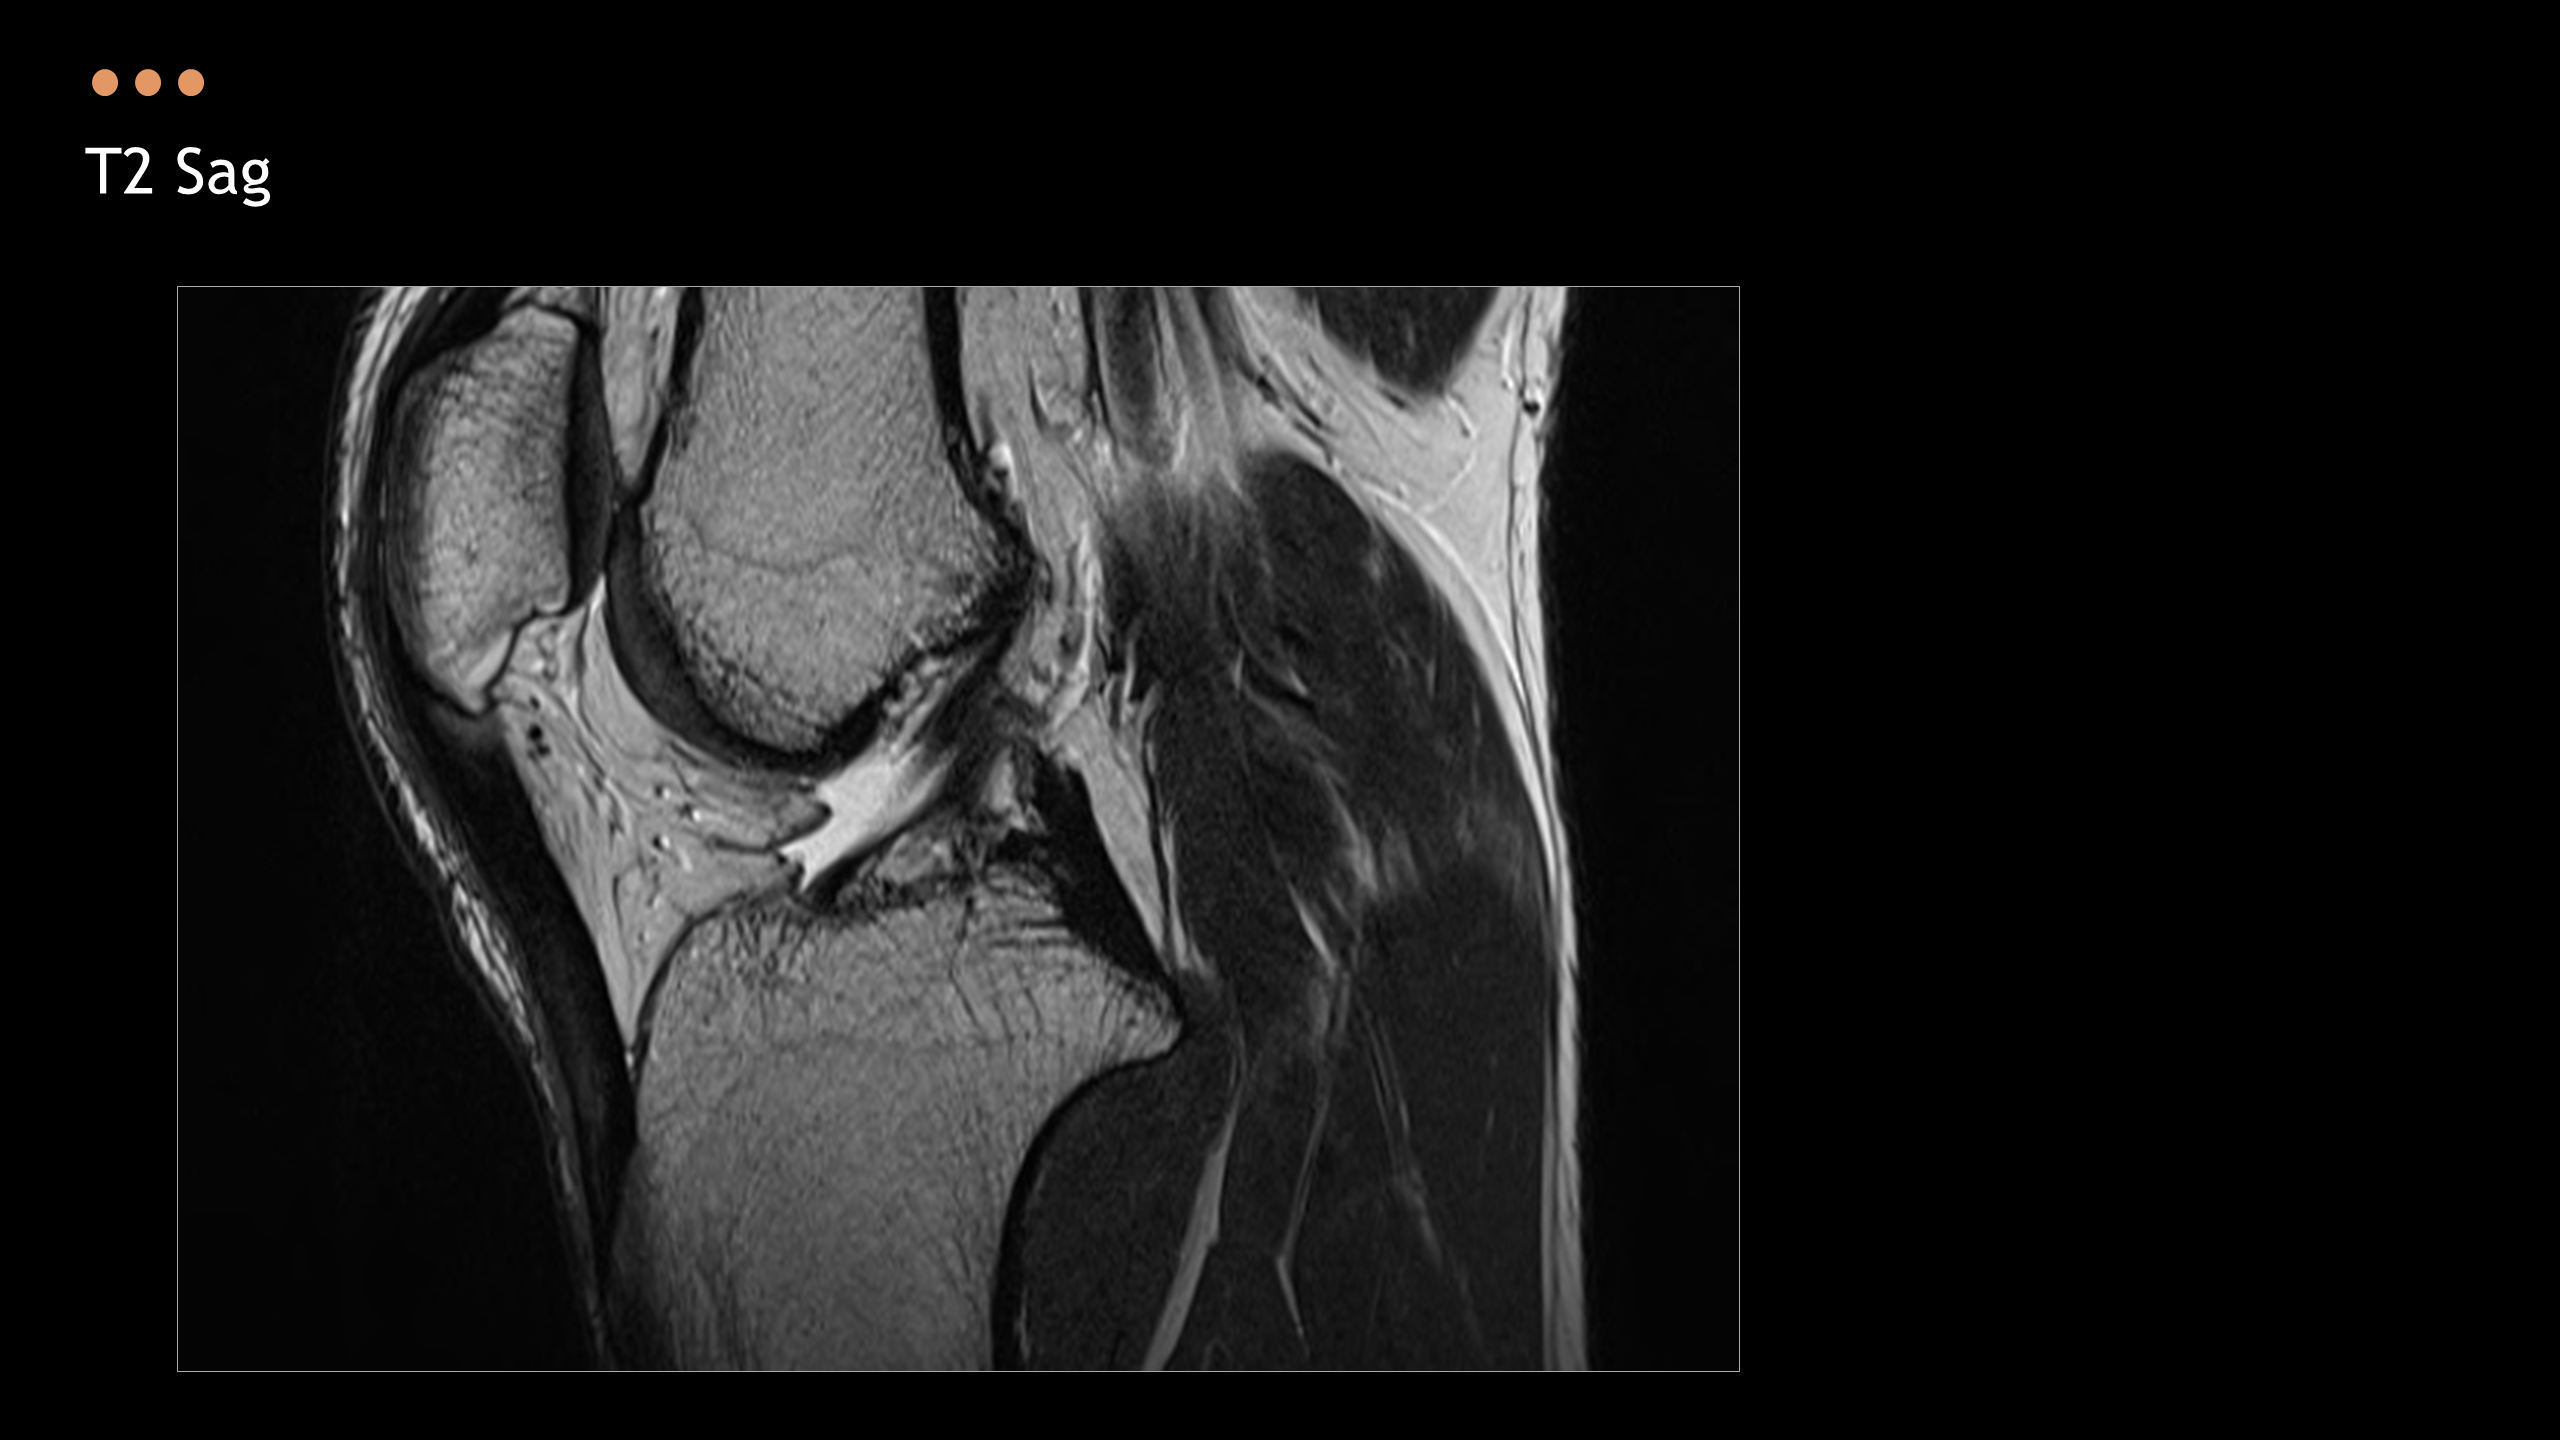

아래의 Normal Knee MR Anatomy를 숙지하고 오셔야, 강의에 어려움이 없습니다.

Detailed Knee MRI Anatomy [대한연부조직한의학회].pdf